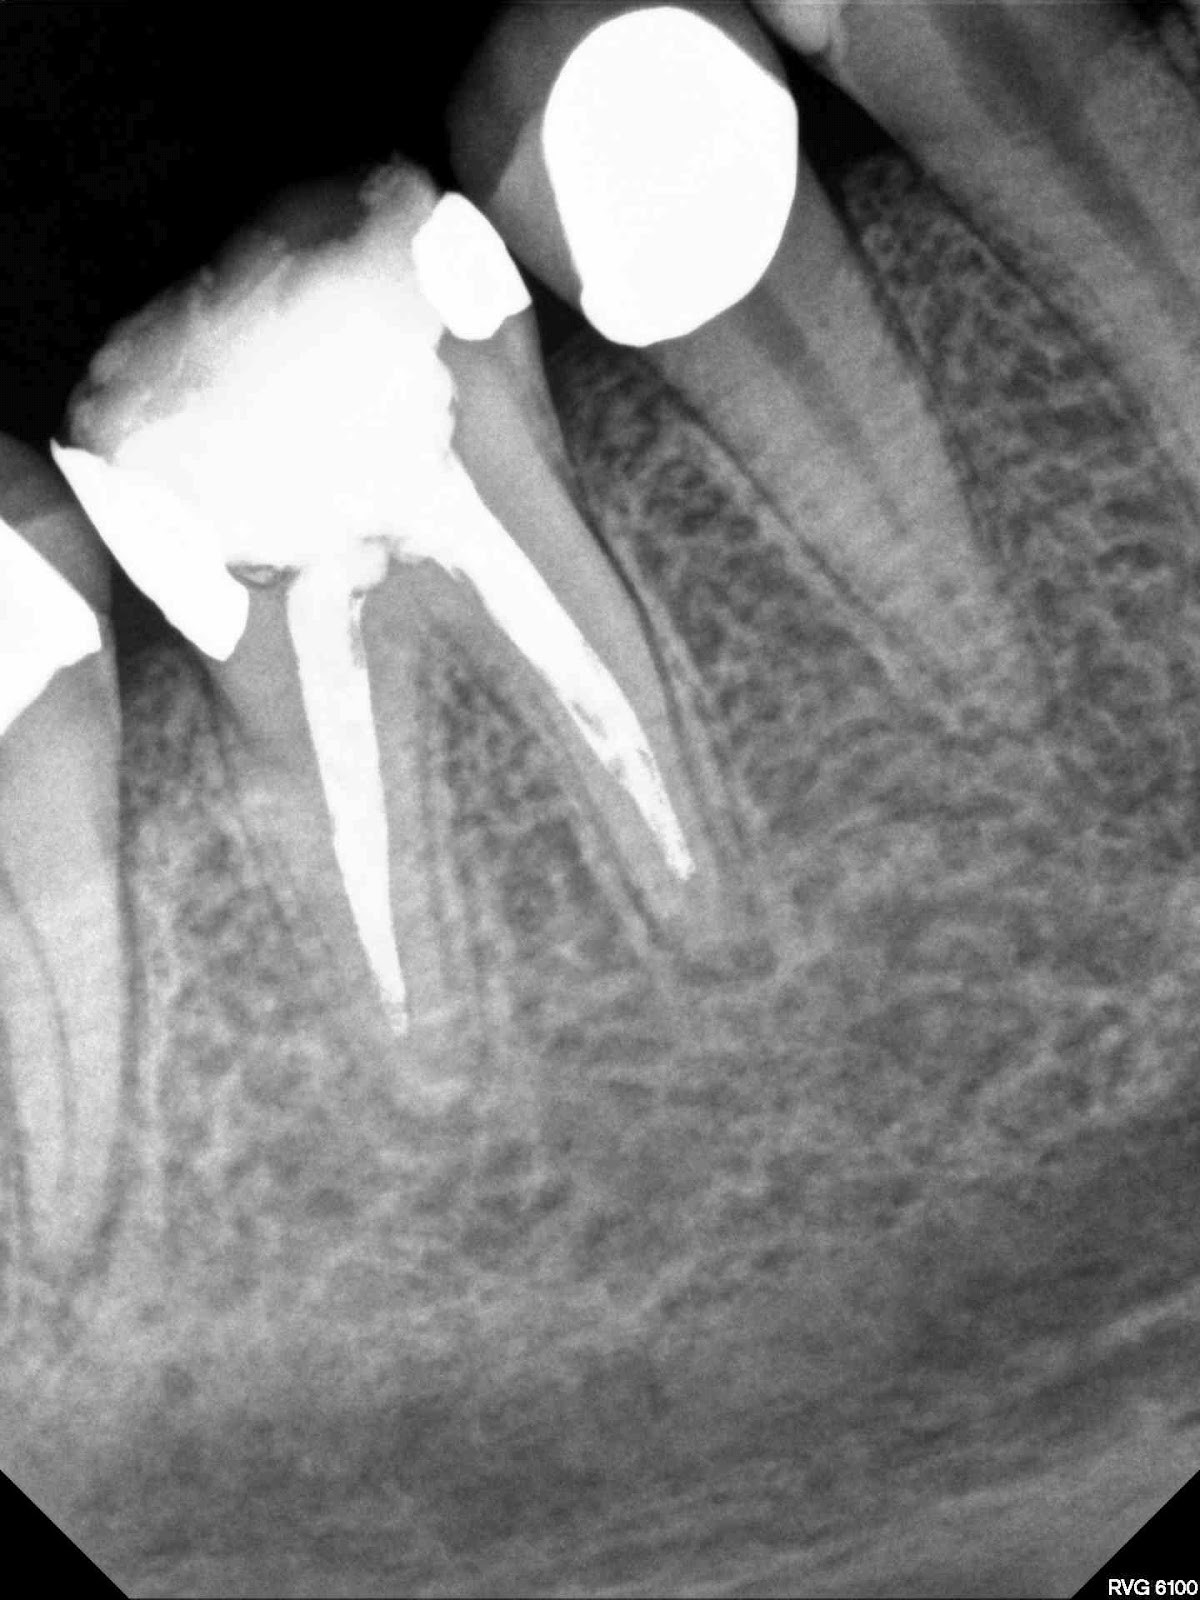

| ML, mid-mesial, and MB apparent. MB2 is probably more of a ribbon fin of off MB. I filled separately. |